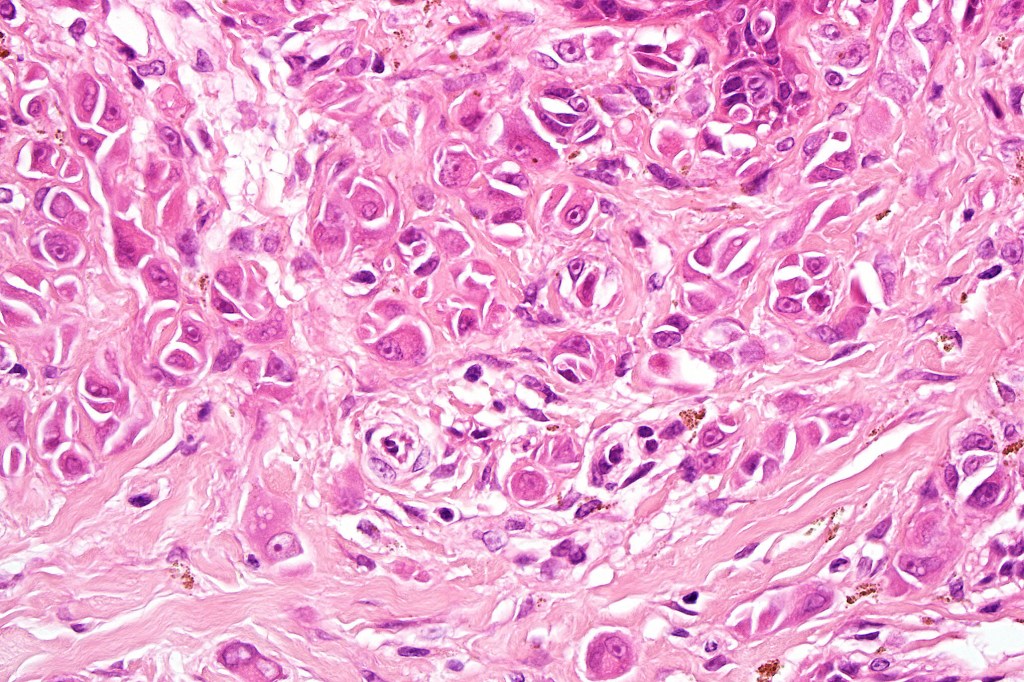

•Spindle, epithelioid and mixed cell variants

•Pleomorphism is almost invariable but affects all of the population to the same extent i.e., the cells & nuclei all look very much the same

•Epithelioid cell variants often show greater pleomorphism and cells can frequently appear bizarre with abundant, sometimes ground glass cytoplasm and large vesicular nuclei with prominent eosinophilic nucleoli, multinucleate cells are often seen

•Intracytoplasmic pseudoinclusions commonly present in epithelioid cells

•Mitoses can brisk in younger patients and should not be taken as indicating melanoma

•Mitoses are restricted to the superficial aspect on the nevus and are never atypical